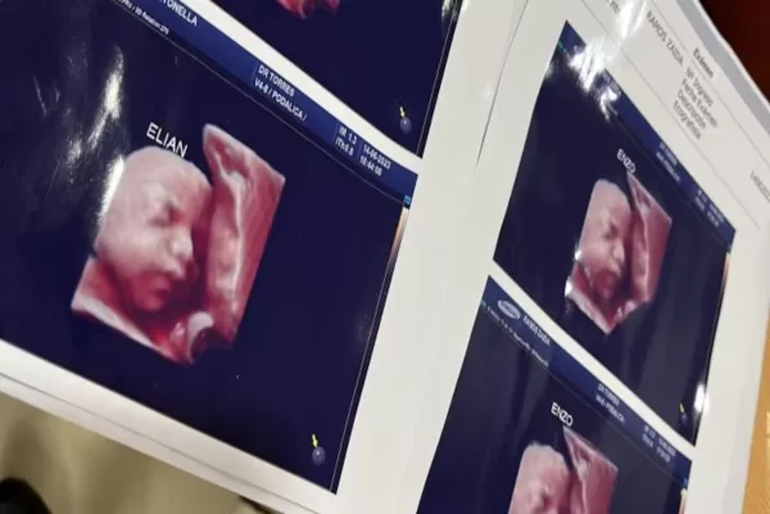

El poder de las redes sociales logró desenmascarar una oscura trama detrás de una clínica privada de Formosa, la cual fue denunciada por varias mujeres. Al lugar se lo acusa de entregar la misma ecografía 5D a sus pacientes embarazadas.

En medio de la consternación, la mujer le mostró que tenía la misma foto de la ecografía y es en ese momento donde comenzaron a revelar el fraude que habían sufrido.

"Ese es mi bebé!!", le respondió la usuaria junto a la imagen. Al instante la persona que había subido la imagen le respondió sin comprender lo que pasaba: "Ay no, es la misma".

Con la viralización de la noticia, otras pacientes pudieron notar que también habían sido víctimas de esta estafa con ecografías: "Por ahora somos tres mamás a las que una clínica estafó con una foto de un bebé que no es el nuestro", sostuvo una de ellas en Twitter.